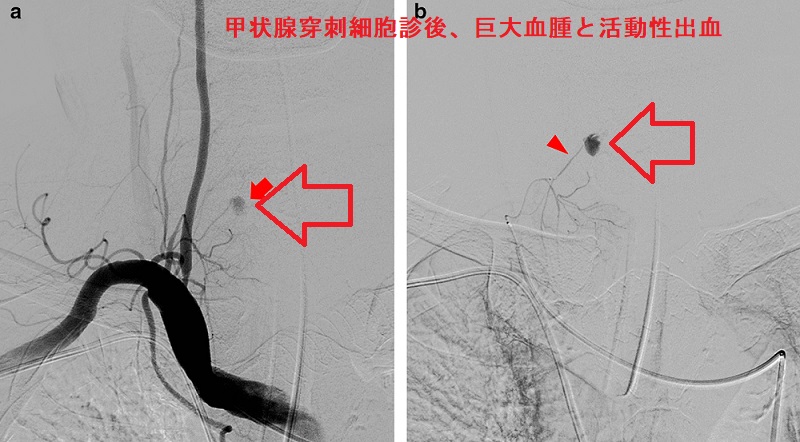

甲状腺穿刺細胞診後の巨大血腫・活動性出血

(報告例)甲状腺穿刺細胞診から3時間後、重度の呼吸困難をきたし、気管内挿管。造影CTで気管を圧排する巨大血腫(上の写真左)と、活動性出血を示唆する造影剤の漏れ(Extravasation)(上の写真右)を確認。

右鎖骨下血管造影にて下甲状腺動脈(ITA)からの活動性出血を同定し、n-ブチルシアノアクリレート(NBCA)を用いた経カテーテル動脈塞栓術(TAE)で止血したそうです(下の写真)

(BMC Surg. 2021 Apr 27;21(1):220.)。

上甲状腺動脈分枝からの穿刺細胞診後出血に対し、ゼラチンスポンジの経カテーテル動脈塞栓術(TAE)を行った報告もあります(第68回 日本甲状腺学会 P19-2 甲状腺穿刺後出血に対して,経カテーテル的動脈塞栓術(TAE)により止血を得られた一例)。